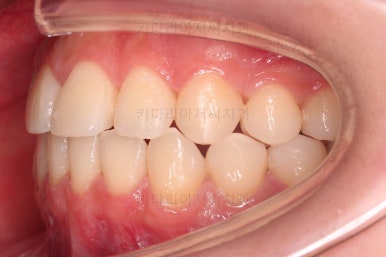

초진 시의 다른 부위들 사진입니다.

약간의 주걱턱 느낌에 약간의 돌출감, 전반적인 치열의 가지런한 느낌은 나쁘진 않았지만 약간의 불량한 교합상태였어요.

다른 부분은 크게 바꾸지 말고 약간의 교합 조절과 어금니 치료에 초점을 맞춰서 교정치료 계획을 잡았습니다.

전후사진을 비교해 볼게요.

약간의 주걱턱, 돌출입은 고칠 의사가 없어서 그대로 유지하였고 주걱턱 패턴으로 인한 부정교합 부분을 개선했으며 무엇보다 중요한 것은 쓰러져서 많이 썩어있던 치아를 자칫 치료 못할 뻔 했는데 교정치료와 병행하여 훌륭하게 치료를 하여 살려 썼다는 점입니다.